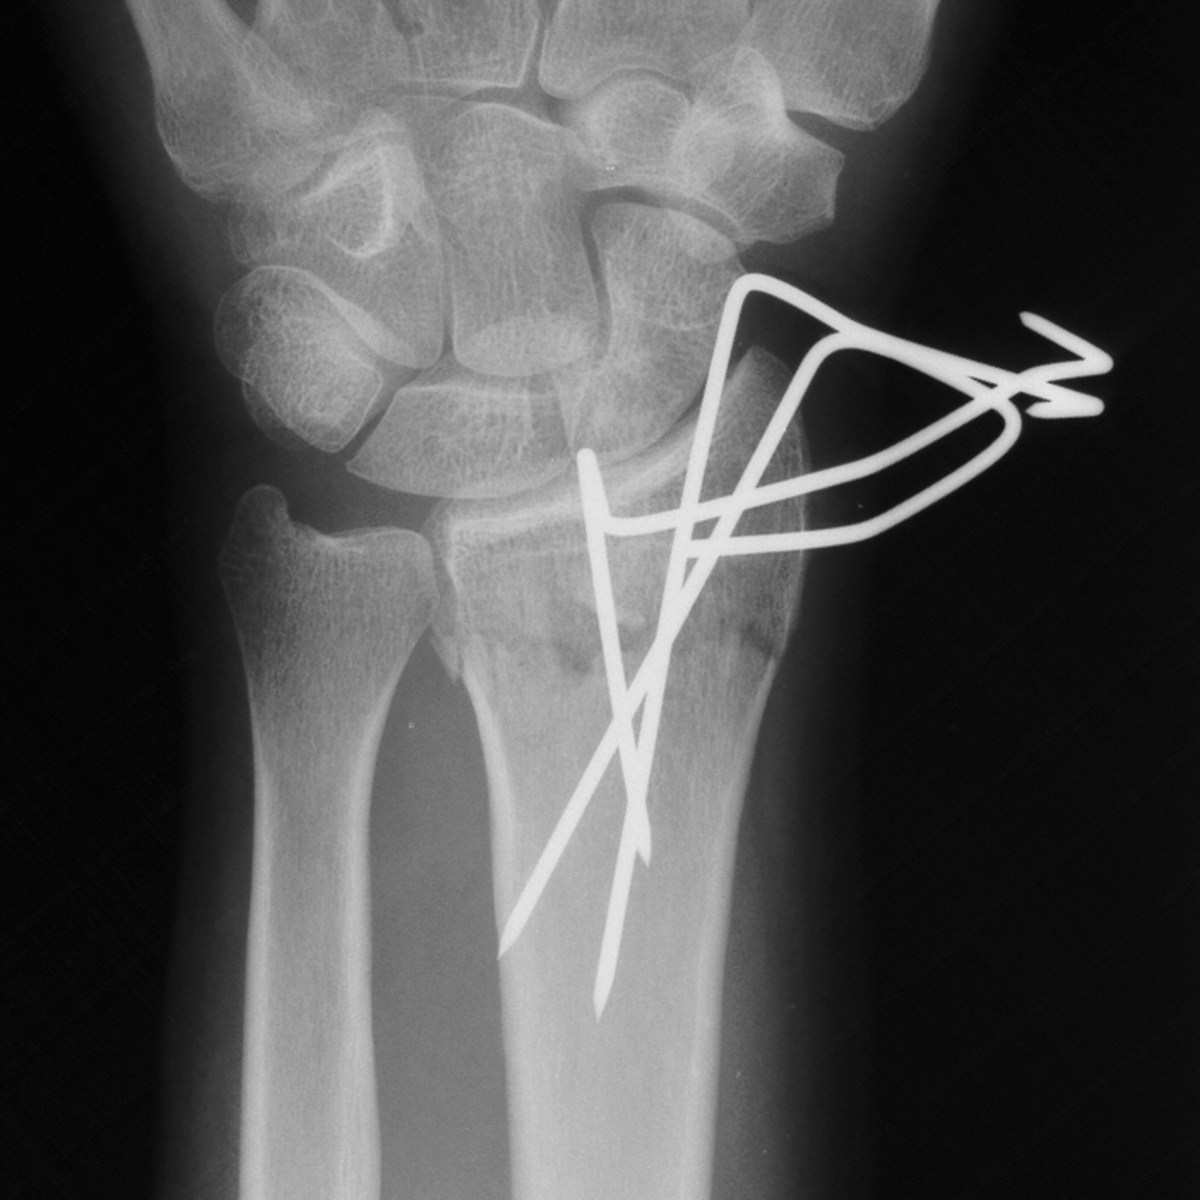

| Case 6 Extraarticular distal radius fracture with angulation and dorsal comminution. |

| Attempts at

closed reduction alone were unsuccessful. |

| Percutaneous

fracture stabilization with three pins via the

dorsal radial tubercle, radial styloid and FCR

portals. |

| Pins were left

protruding and bent to overlap. |